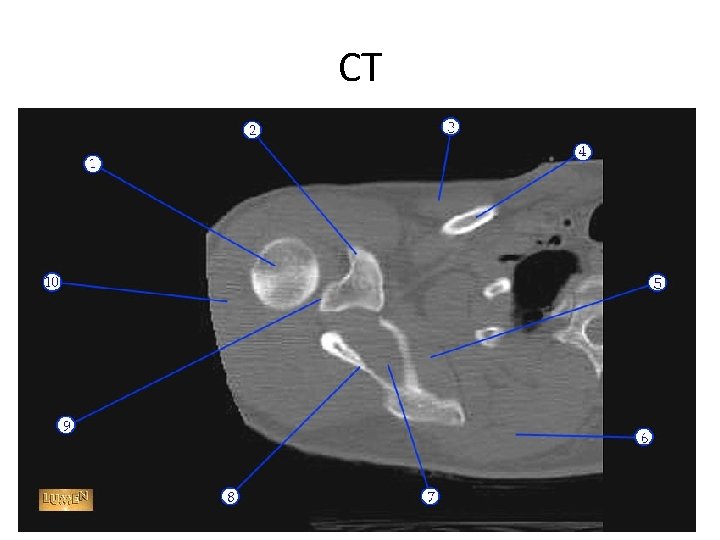

1. 2. 3. 4. 5. 6. 7. 8. 9. 10. coracoid subclavius pectoralis major clavicle Subscapularis Serratus anterior Infraspinatus spine Deltoid muscle. Humeral head.

CT